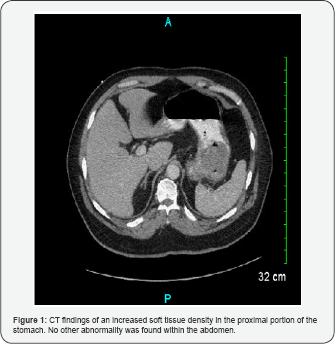

The patient was a 55-year-old Hispanic man who presented with anemia (hemoglobin (Hg) 7.6g/dL, hematocrit (Hct) 26%), epigastric abdominal pain, and melena. The patient had these symptoms for the past couple of months and they worsened 5 days prior to admission. His past medical history included hyperlipidemia and type 2 diabetes mellitus. On physical exam, he had a soft abdomen that was tender in the epigastric area, and had normal bowel sounds. On CT scan, an increased soft tissue density was identified in the proximal portion of the stomach (Figure 1). No other abnormality within the abdomen was found. Laboratory tests were unremarkable except for low hemoglobin and hematocrit. Preoperative serum tumor markers, such as alpha-fetoprotein (AFP), beta human chorionic gonadotropin (β-hCG), carcinoembryonic antigen (CEA), or lactic dehydrogenase (LDH) were not evaluated. Upper gastrointestinal endoscopy showed a polypoid mass (Figure 2). Due to continued bleeding, surgery was considered necessary and a was performed. H&E and immunohistochemical (IHC) stainings, including desmin (Ventana, Tucson, Arizona), MyoD1 (Cell Marque, Rocklin, California), neurofilament (Ventana, Tucson, Arizona), SALL-4 (Biocare Medical, Concord, California), and synaptophysin (Ventana, Tucson, Arizona), were performed

CT and ultrasound findings typically show a heterogeneous mass with cystic and solid components as well as fat and calcifications [4,19]. The present mass showed soft tissue density without any fat or calcifications. Lack of the typical teratoma findings on CT led to different differential diagnosis including gastric carcinoma and gastrointestinal stromal tumor The definitive diagnosis is only possible after taking into consideration the results from surgical excision with histological examination.